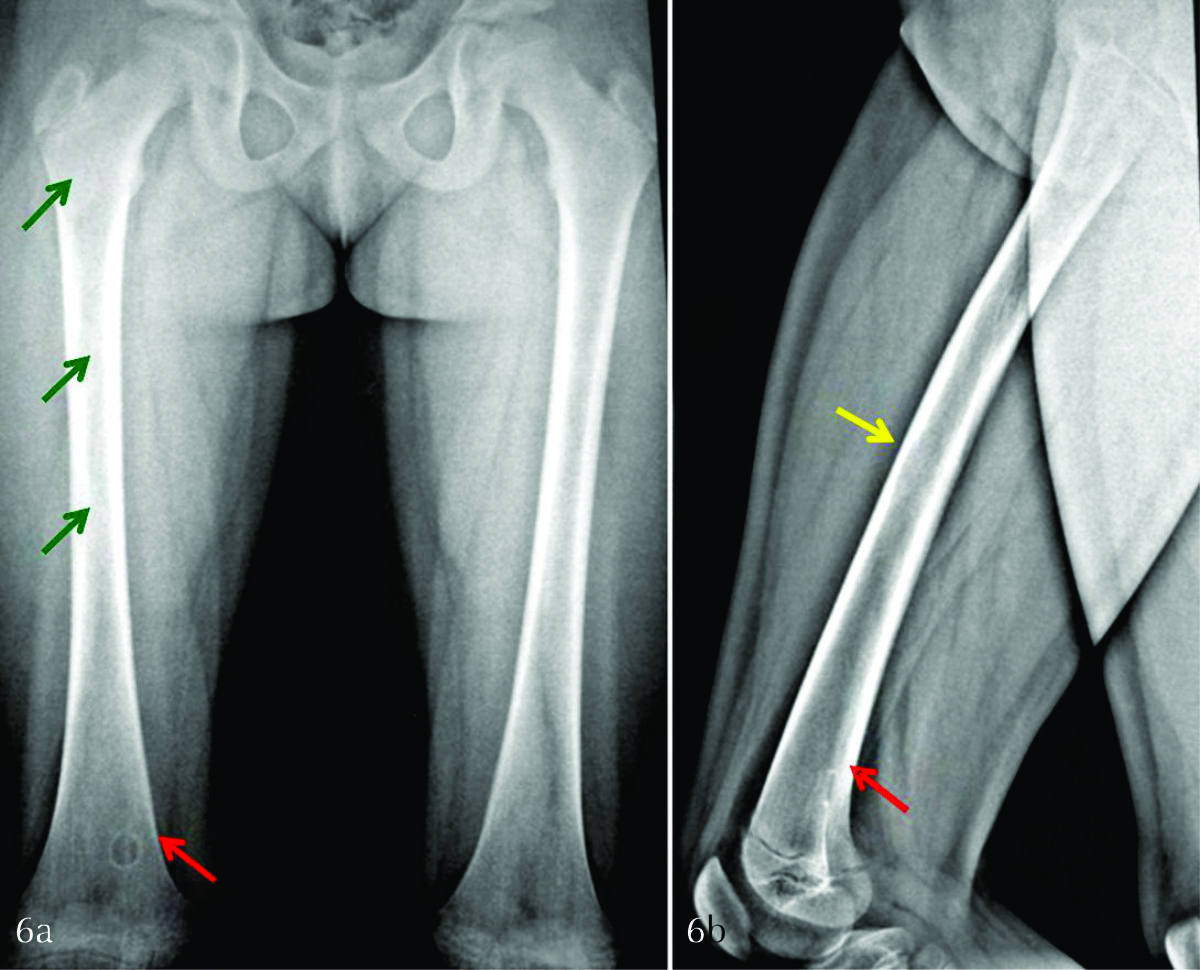

Figura 6

a) Radiografía bilateral en proyección anteroposterior de fémur. b) Radiografía de fémur derecho de perfil. Se identifican lesiones radiolúcidas incipientes, en diáfisis de fémur derecho (flechas verdes), con festoneado endóstico (flecha amarilla). A su vez, se aprecia una lesión cortical, lítica, geográfica, bien delimitada, con anillo esclerótico (1b), en probable relación a fibroma no osificante (flechas rojas).